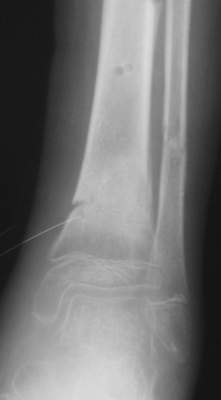

A> Это сросшийся перелом малоберцовой кости. И ложный сустав

A> н\3 б\берцовой кости.

Нашел в комп-ре схожий случай:

1) з/репозиция, 2) фиксация 2 спицами, 3) аппарат, 4) фиксационные

спицы удалены...

А можно было наложить аппарат и по поводу ложного сустава...

По крайней мере не было бы укорочения (пусть и в 2 см)...